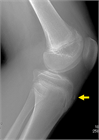

1. 膝蓋腱の牽引による脛骨粗面部の骨端症で、12歳前後の活動性の高い男児に好発する。

1. 脛骨粗面の疼痛、腫脹、熱感を訴え、病初期はスポーツ活動の継続が可能であることが多い。

1. 初期病変の描出には超音波が優れ、病期が進行すると単純エックス線でも描出可能となる。